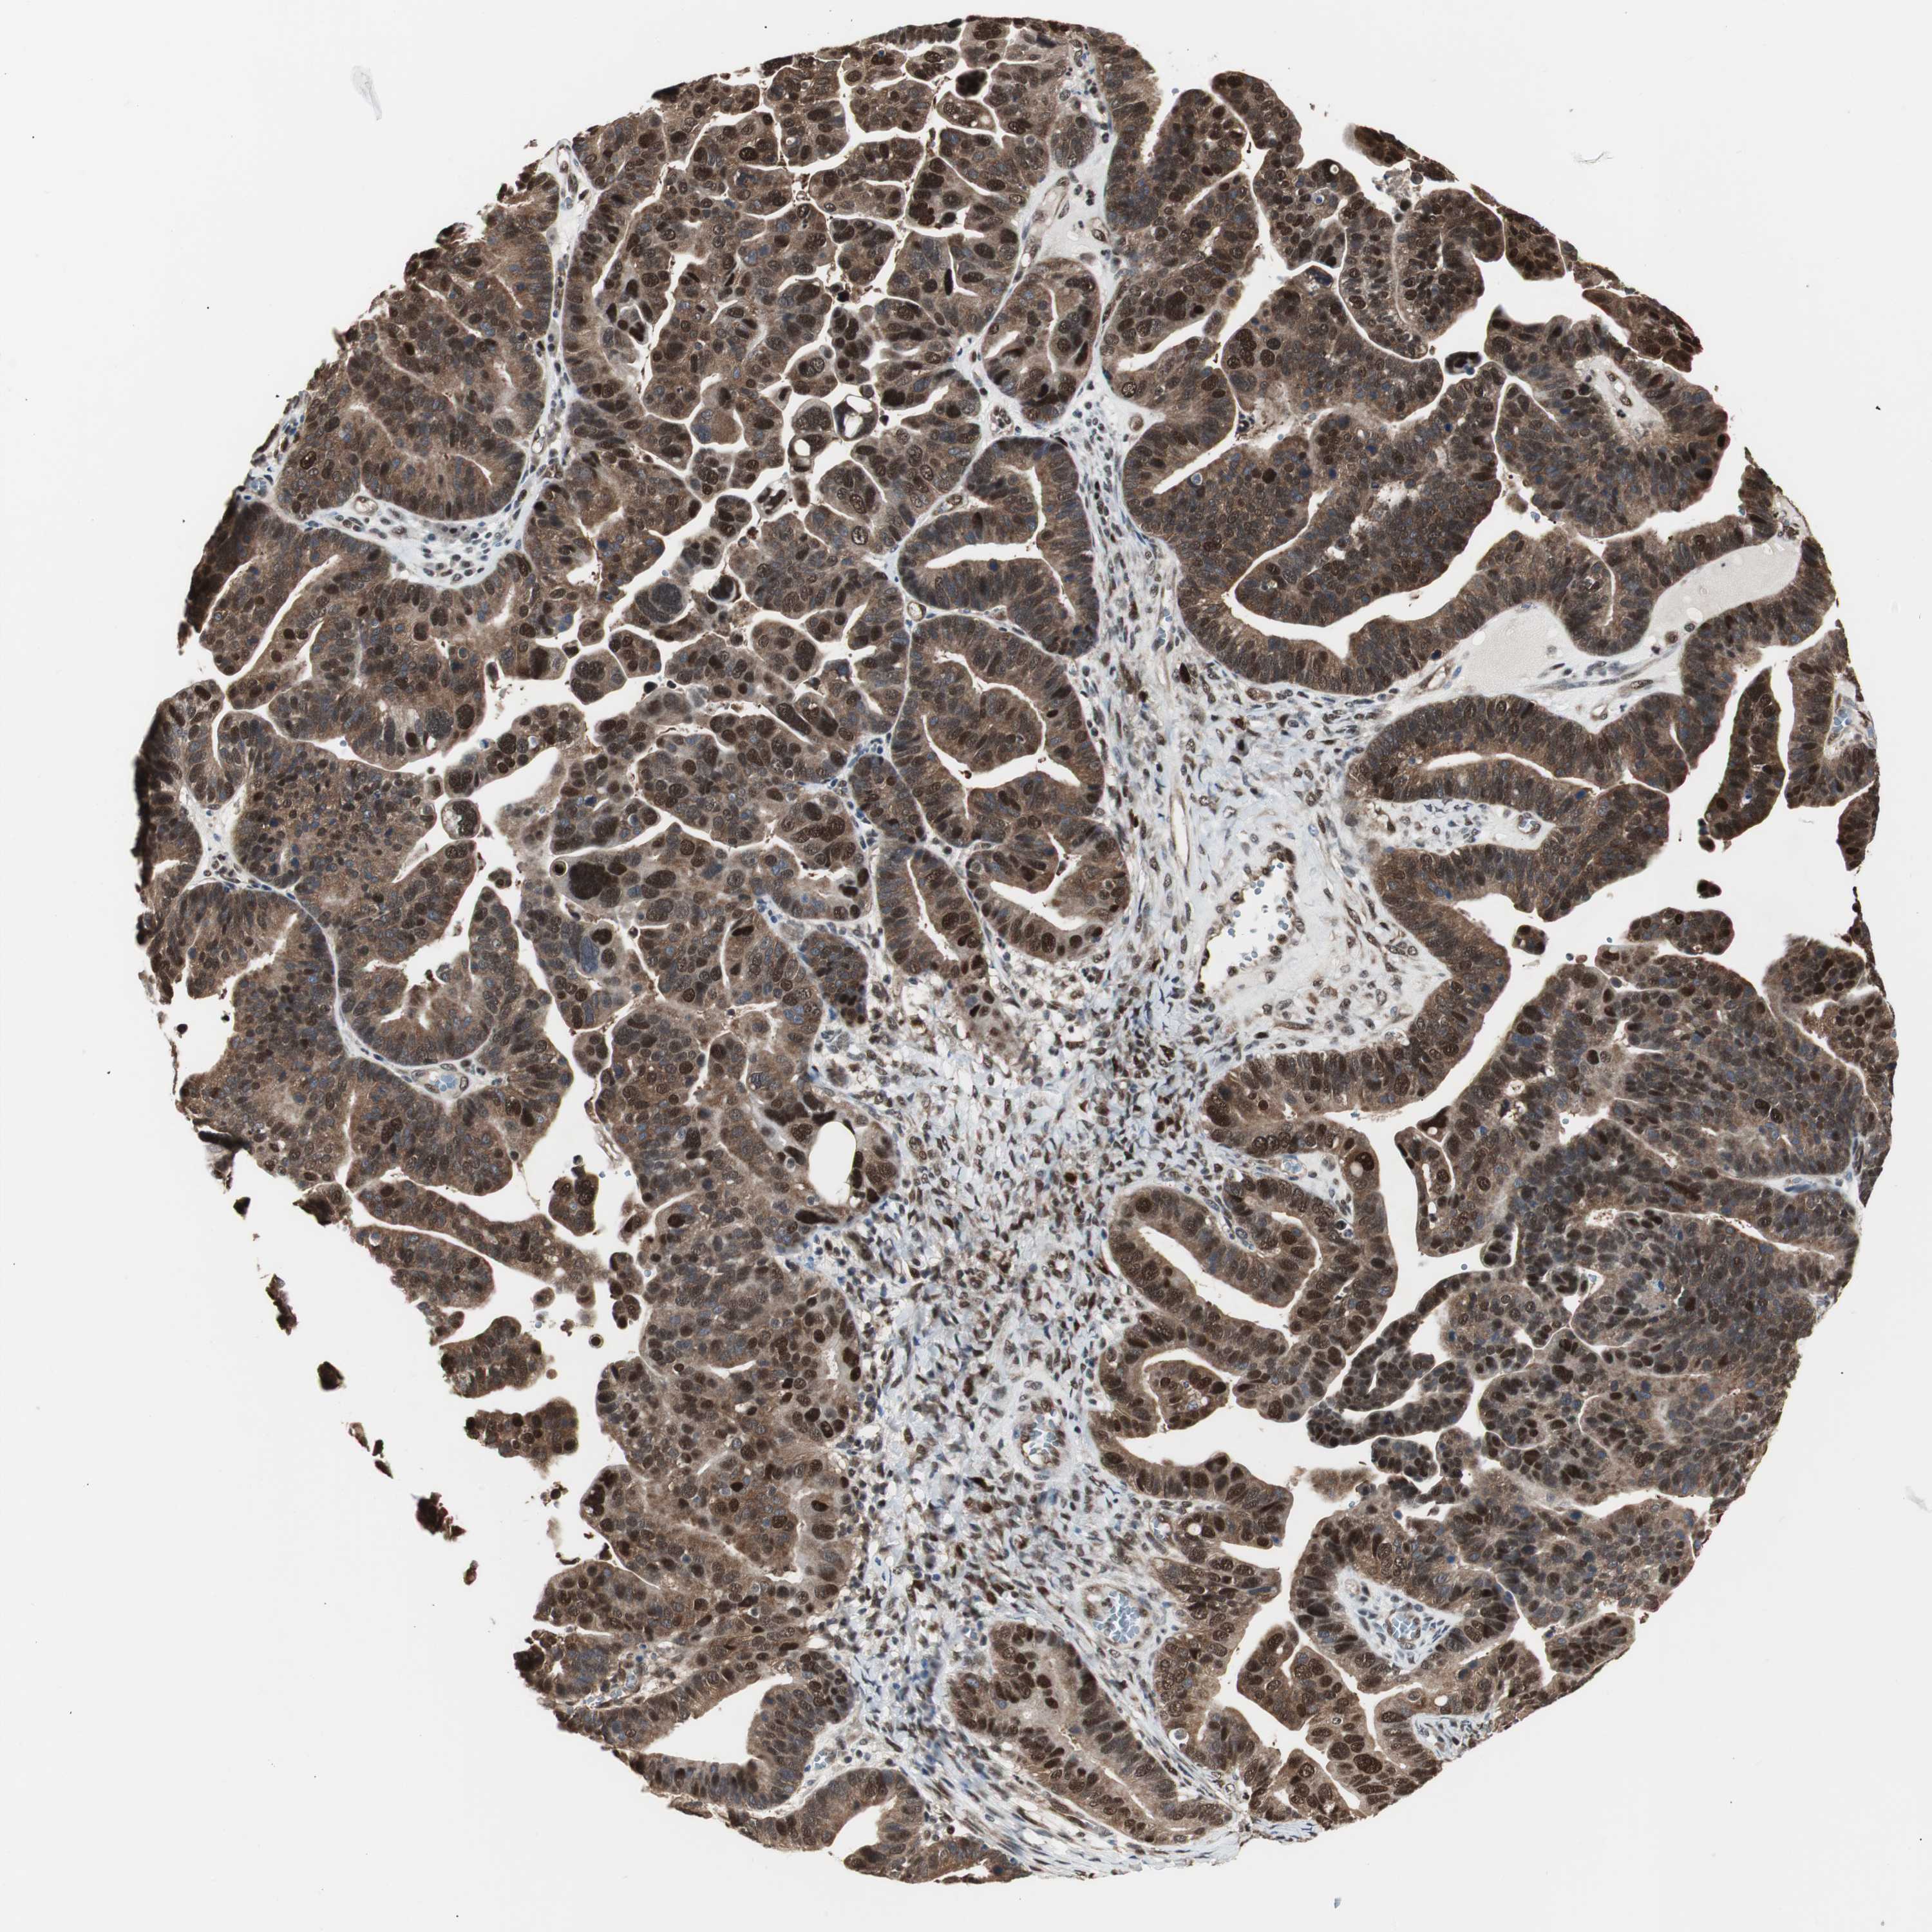

OVARIAN CANCER - Protein expressioni

A mouse-over function shows sample information and annotation data. Click on an image to view it in a full screen mode. Samples can be filtered based on level of antibody staining by selecting one or several of the following categories: high, medium, low and not detected. The assay and annotation is described here.

Note that samples used for immunohistochemistry by the Human Protein Atlas do not correspond to samples in the TCGA dataset.

Antibody stainingi

Antibody staining in the annotated cell types in the current human tissue is reported as not detected, low, medium, or high, based on conventional immunohistochemistry profiling in selected tissues. This score is based on the combination of the staining intensity and fraction of stained cells.

Each image is clickable and will lead to virtual microscopy that enables deeper exploration of all samples and also displays staining intensity scores, fraction scores and subcellular localization as well as patient and tissue information for each sample.

HPA028758

CAB007783

Carcinoma, NOS

Carcinoma, endometroid